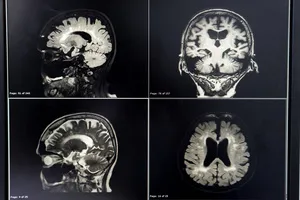

뇌졸중

갑자기 심한 어지럼증이 느껴지고, 한쪽 팔다리에 힘이 없거나 감각이 이상해지고, 말이 어눌해지거나 시야가 흐릿해진다면 뇌졸중을 의심해야 합니다. 이러한 증상들은 뇌혈관에 문제가 생겨 뇌세포가 손상될 때 나타날 수 있습니다. 뇌졸중은 골든타임을 놓치면 후유증이 심해질 수 있으므로, 즉시 병원을 찾아 정확한 진단과 치료를 받는 것이 중요합니다.

뇌졸중 치료는 혈전 용해, 혈압 조절, 수술 등 다양한 방법이 있으며, 환자의 상태에 따라 적절한 치료를 선택합니다.